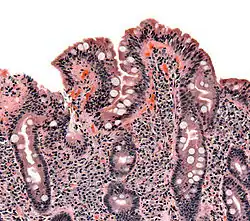

Gastrointestinal Physiology looks at the functioning of the Gastro-Intestinal (GI) system. The four basic functions of the GI system are digestion, absorption, motility and secretion. Digestion describes how ingested food is broken down into smaller biochemical components; absorption how the products of digestion are absorbed into the body; motility how food and waste products are moved from mouth to anus; and secretion how digestive juices etc. are controlled and secreted. About 9 liters of fluid pass through the GI system every day, and of these only two are taken by mouth, the rest represents secretions by the system itself.

The digestive system is the body's major interface with the out side world, and as such it is richly supplied with immune cells, indeed by some estimates 80% of the bodies immune cells are in the GI tract.